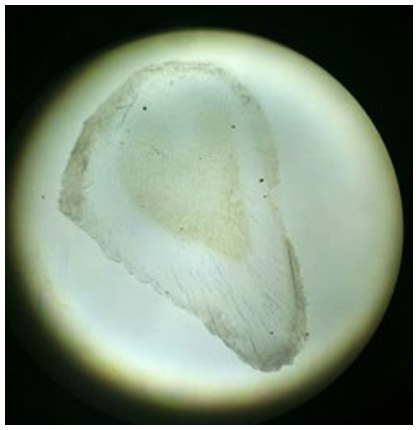

On ground sectioning of the tooth, it showed hypoplastic enamel with reduced thickness and loss of enamel at few places. There was presence of atubular osteodentin along with alterations in the atypical dispositions of dentinal tubules. Moreover, there existed irregular dentin in the cervical portions and interglobular dentin in the coronal region. The enamel rods showed a fish scale pattern and enamel spindles were seen focally. Predominantly tubular dentin was present. Dentinoenamel junction was not scalloped which was similar to deciduous teeth (Figure 2.1, 2.2, 2.3, 2.4). The complete healing of the lesion took 4 weeks; subsequently, the infant, revised at the 1-year follow-up visit.

Figure 2.2: Ground section of neonatal tooth showing Dentin.

Dentin is the layer beneath the enamel, containing less inorganic content with greater porosity and leathery texture in contrast to mature teeth. The dentin in neonatal teeth may also show wider dentinal tubules (small channels that run through the dentin), indicative of rapid dentin formation, with higher amounts of mineralization.